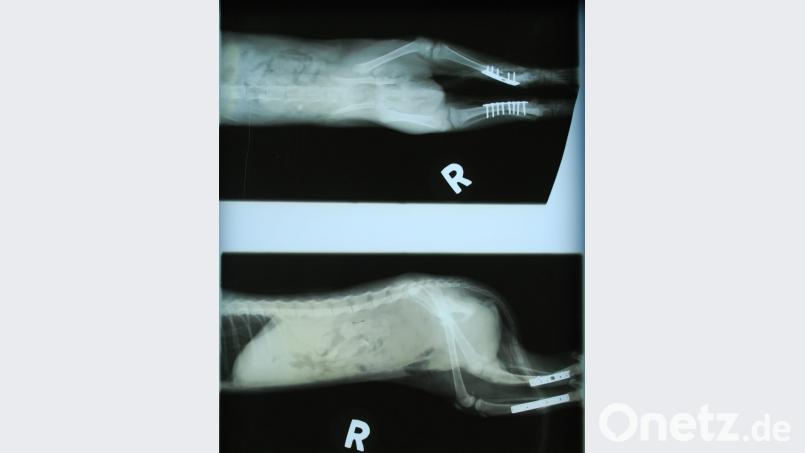

Doch der weigerte sich: "Das ist kein Grund zum Einschläfern. So etwas kann man richten, egal, was es kostet." Daraufhin hat er das Tier angenommen "und nach und nach mit großem Aufwand auf eigene Kosten operiert". Zweimal drei Stunden dauerten Bauchbruch-, Becken und Hüft-OP sowie die Verplattung beider Unterschenkel mit medizinischem Stahl. Nach ein paar Tagen konnte das Kätzchen wieder laufen, mittlerweile ist es vollkommen genesen und erkundet schon neugierig und frech seine Umwelt.